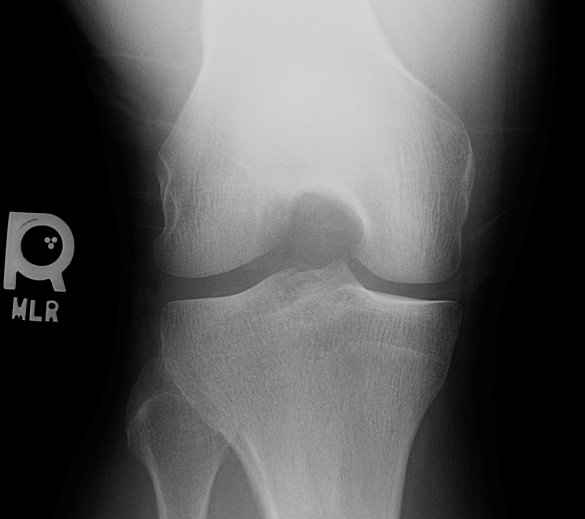

- Click on the image for a larger versionAAP radiograph of the knee. There is a fracture at the lateral tubercle of the tibial spine.